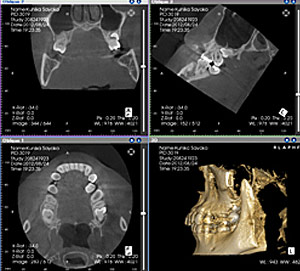

当院では朝日レントゲン工業の歯科用CT(3Dレントゲン)AUGEを導入しています。

歯科専用に開発されたCTで、医科用CTのように横になる必要がなく、短時間で済みますので、被曝量も10分の1程度に抑えることができます。

通常のレントゲンに比べて、より詳細に患者様のお口の中の状態を把握することができます。

具体的には、現在のそれぞれの歯の位置、アゴの骨の状態、まだ生えてきていない親知らずの状態など、口腔内のより多くの情報が得られるため、診断、そして治療計画をつくるのに非常に役立ちます。

また、従来のレントゲンでは平面的な画像でしか状態を見ることができませんでしたが、CTでは立体的に状態を見ることが可能です。この点でも治療を進めていく上で非常に有効です。